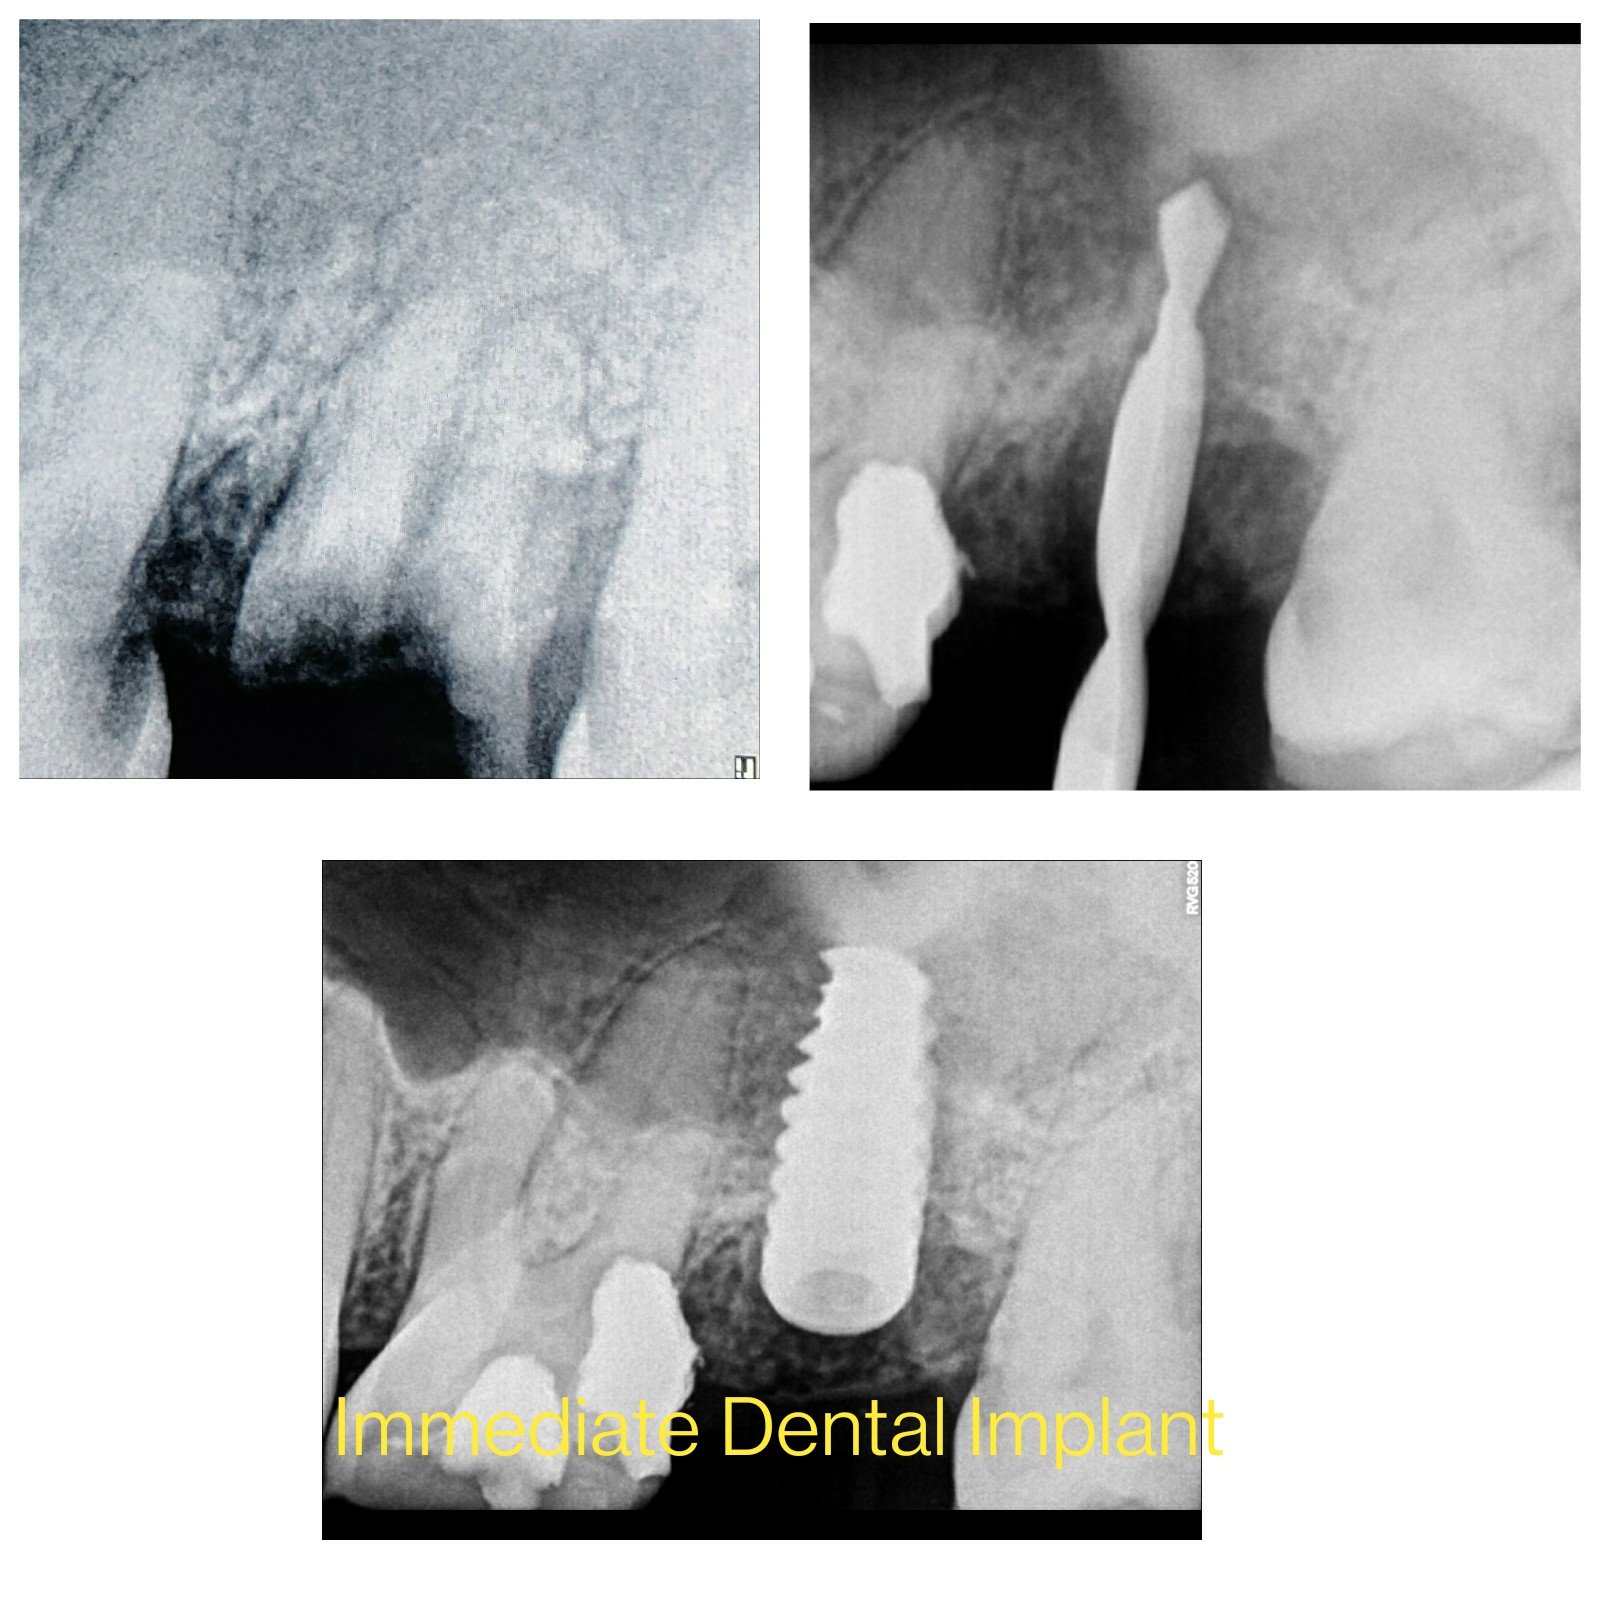

Dental implant surgery is a procedure that replaces tooth roots with metal, screwlike posts and replaces damaged or missing teeth with artificial teeth that look and function much like real ones.

Dental implant surgery can offer a welcome alternative to dentures or bridgework that doesn't fit well and can offer an option when a lack of natural teeth roots don't allow building denture or bridgework tooth replacements.How dental implant surgery is performed depends on the type of implant and the condition of your jawbone. Dental implant surgery may involve several procedures. The major benefit of implants is solid support for your new teeth — a process that requires the bone to heal tightly around the implant. Because this bone healing requires time, the process can take many months.

- Immediate